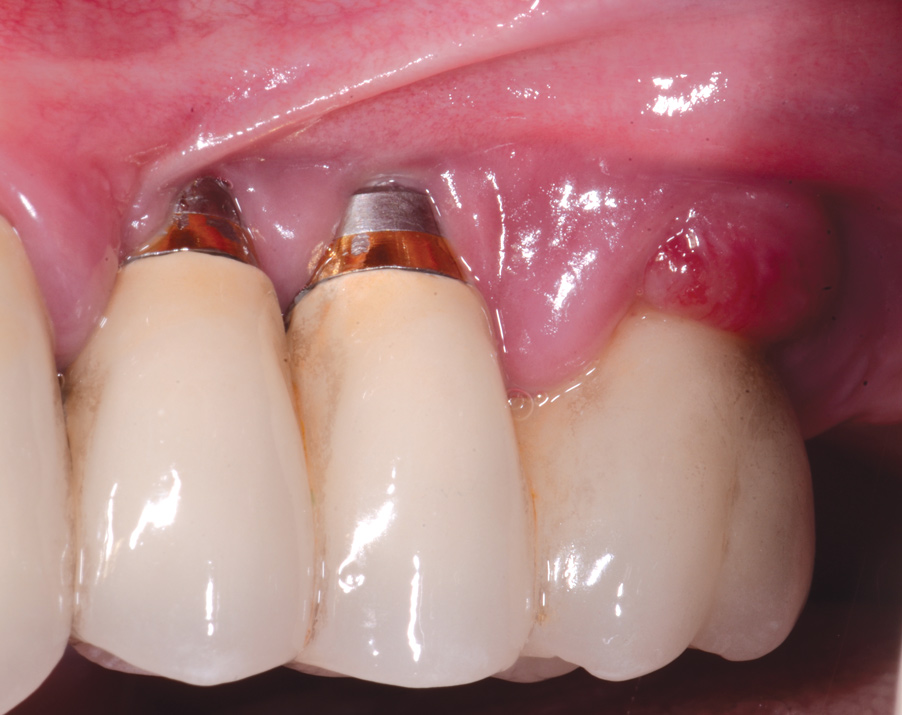

Dental implants have revolutionized the way in which clinicians treat and restore partially and fully edentulous patients and have demonstrated success for managing a broad range of clinical dilemmas. While implants have been highly predictable and have achieved long-term success, they are not immune from complications associated with improper treatment planning, poor surgical and prosthetic execution, material failure, and inadequate or infrequent maintenance. Among these problems are the biologic complications of peri-implant mucositis and peri-implantitis, which are inflammatory conditions in the soft and/or hard tissues surrounding dental implants (Figure 1 through Figure 4).1,2